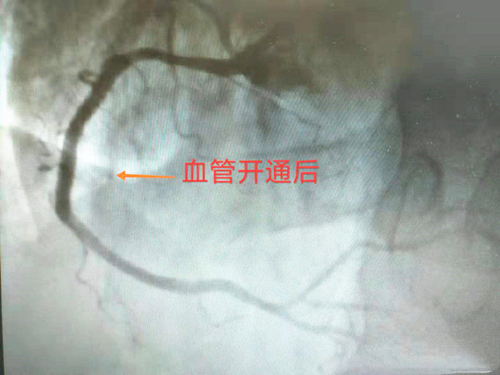

患者冠狀動脈造影提示:三支病變,前降支近段100%閉塞,回旋支近段100%閉塞,右冠狀動脈中段100%閉塞,只靠左側(cè)冠狀動脈的分支血管及側(cè)枝循環(huán)維持血液供應,右冠狀動脈是唯一的一條生命線,若此血管不開通,后果不堪設想,隨時可能出現(xiàn)心跳驟停、惡性心律失常、猝死等意外情況。手術(shù)中,患者惡心、嘔吐加重,心率、血壓持續(xù)下降,醫(yī)護人員立即給予藥物維持生命體征,并快速順利的于右冠狀動脈中段置入支架一枚。開通血管后患者疼痛癥狀緩解,心率、血壓恢復正常,直接回病房修養(yǎng)。